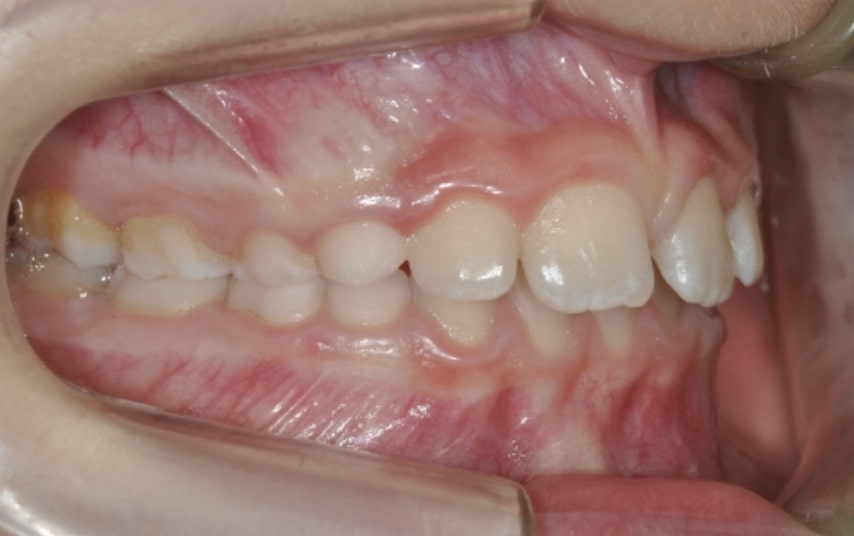

Section Class II division 1 malocclusion

Malocclusion A6 Correction of Mandibular Retrusion in Growth phase patient | Skeletal Class II | Class II Division 1 malocclusion | Deep bite | Mixed dentition

Clinical examination and diagnosis

- Molar and Canine class 2 on the right side – Molar and Canine clss 1 on the left side

- Increased Overjet

- DeepBite

- Reduced Transversal Diameters

- Deviated Lower Midline 2 mm to the Right